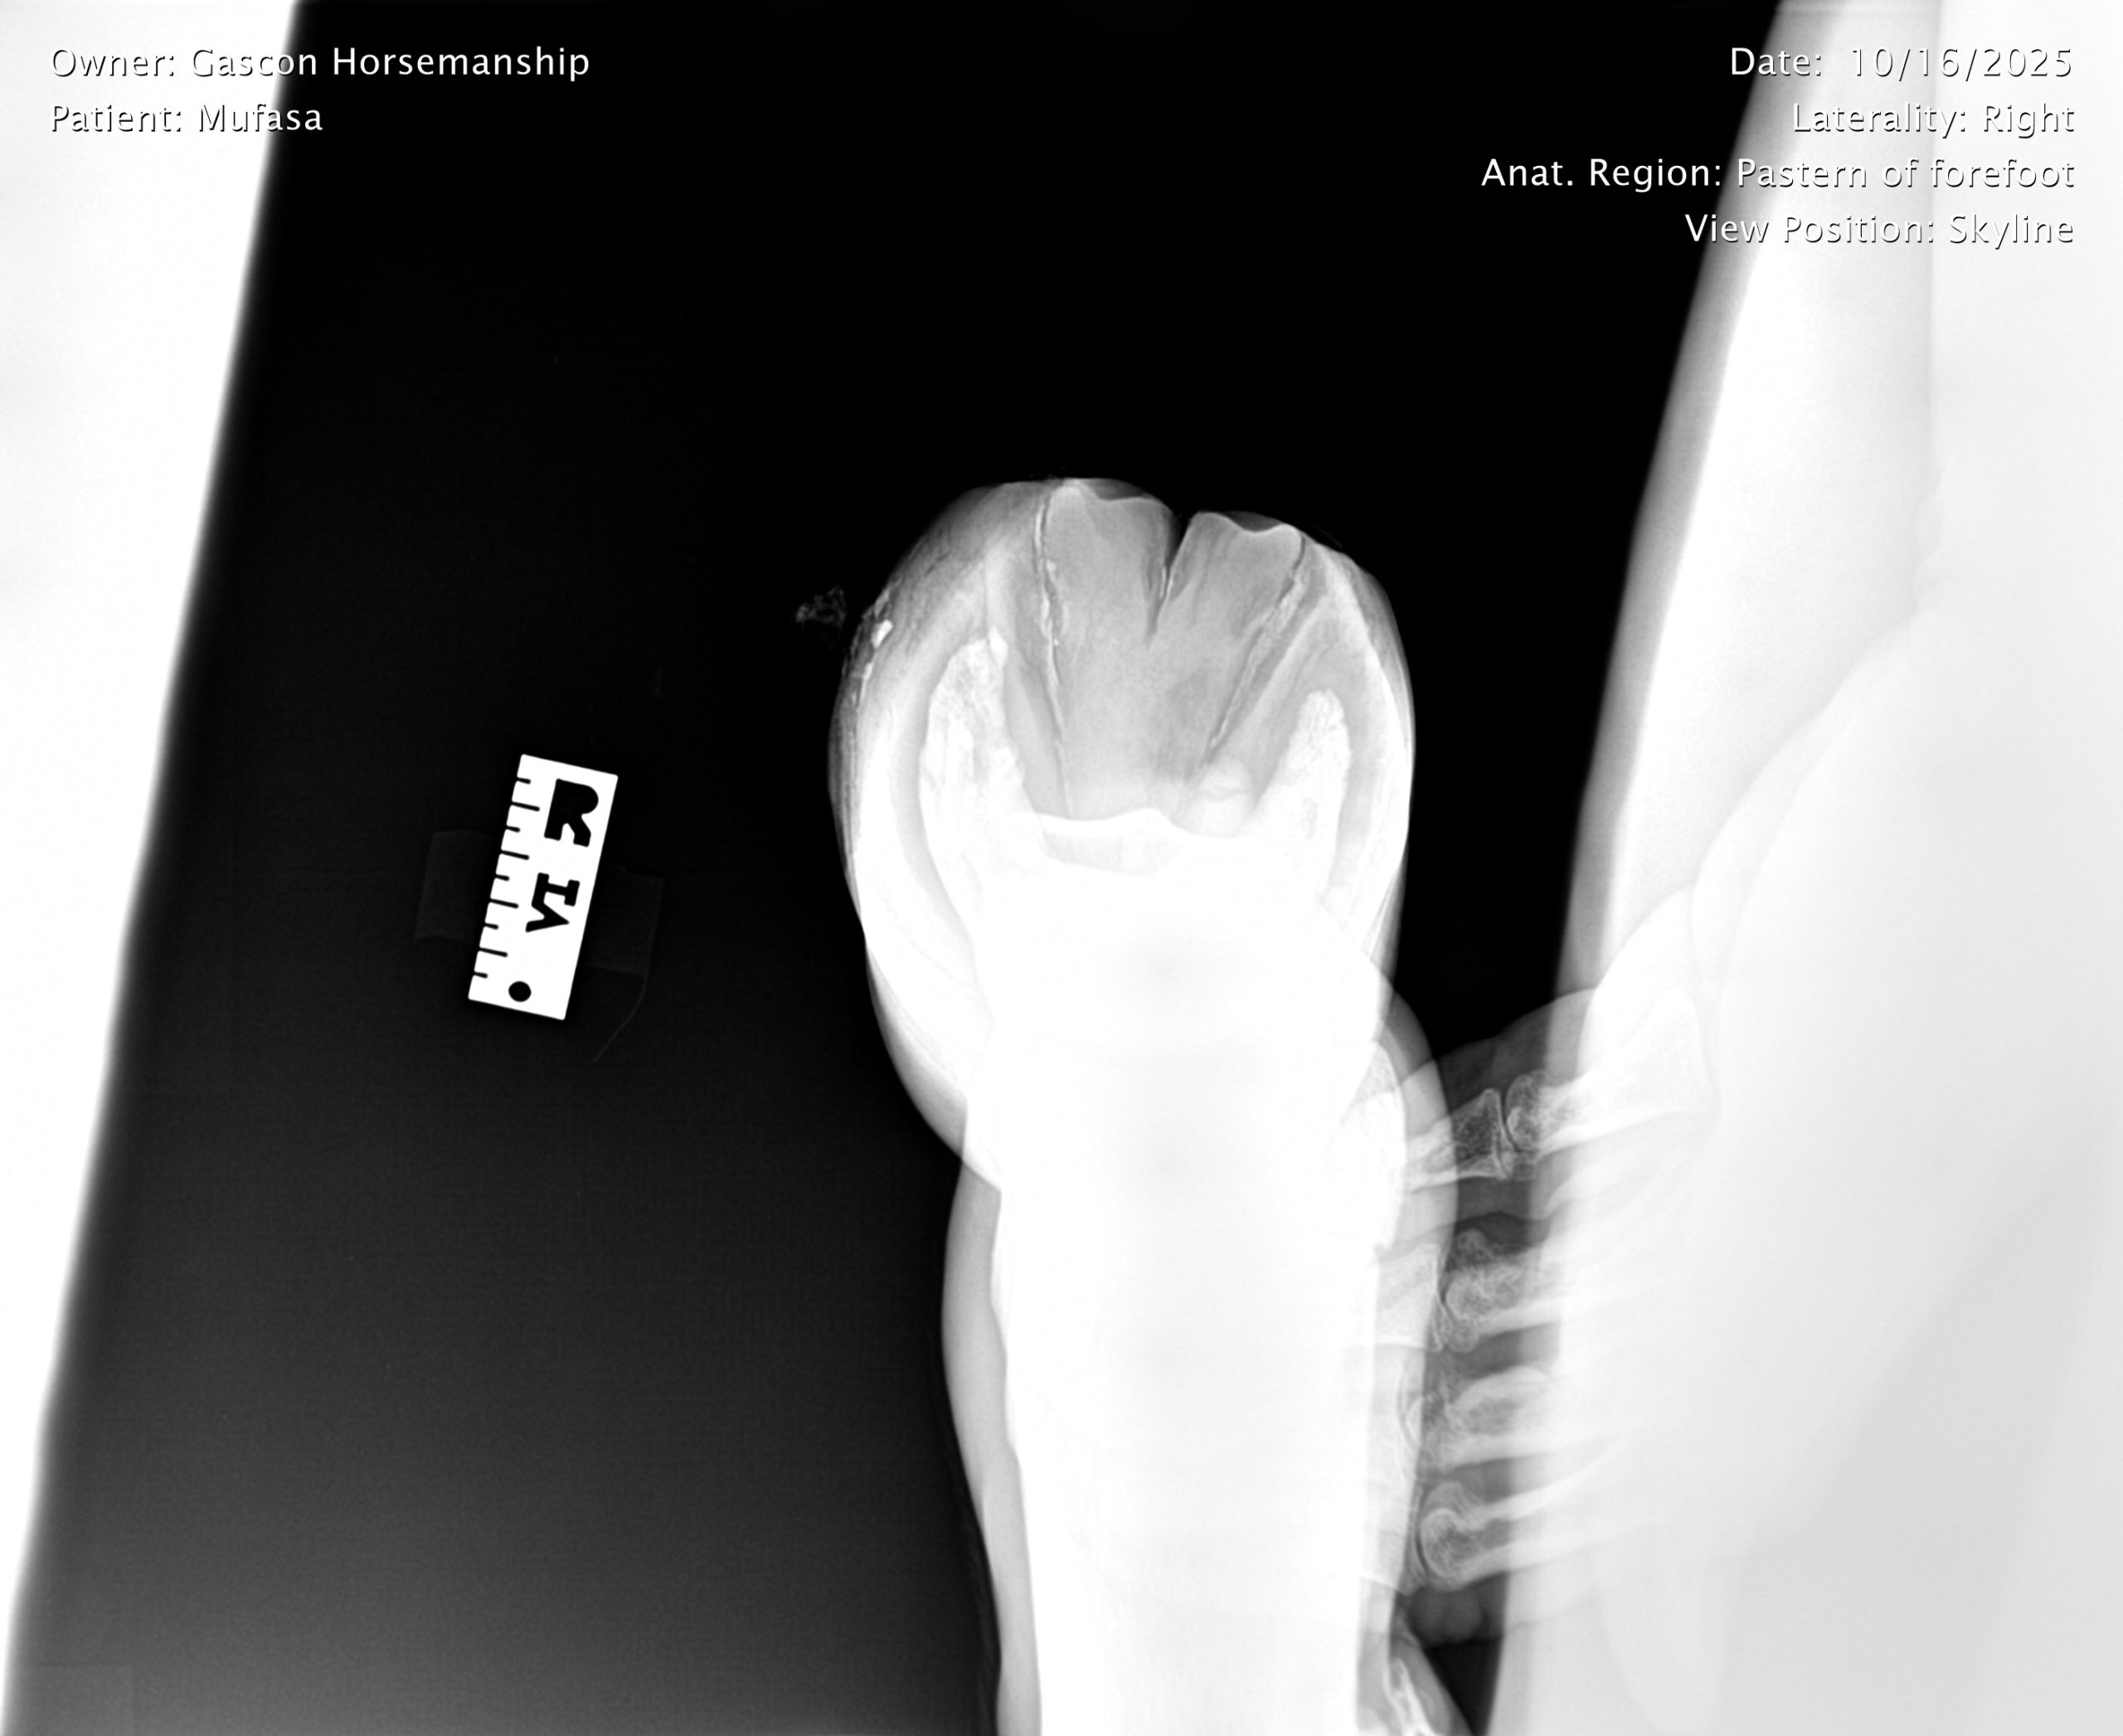

He already has a full pre-purchase exam on file, complete with 25 X-rays included in his album.